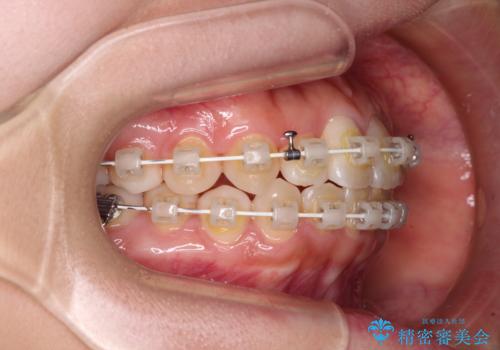

- 審美装置

治療前にお伝えした治療期間は1~1年半でして、1年4か月の期間で終えることができました。

ワイヤー矯正は見た目や装置が当たることでの痛みを気にされる方が多いですが、月1回来院して処置をしてもらうだけで歯並びが整うため、大変お勧めです。